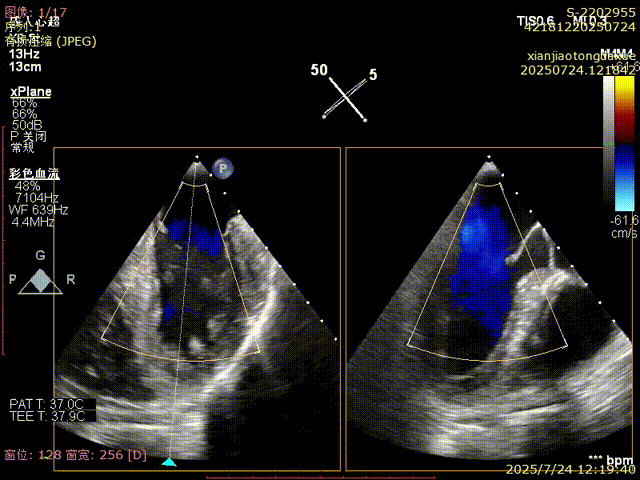

反流得到明显改善

3D视角下反流情况